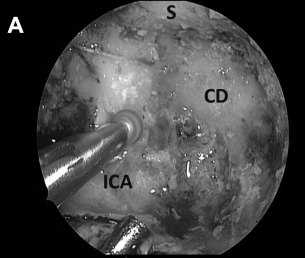

手术方案:通过对侧单鼻孔入路,左侧鼻中隔皮瓣切开并进行蝶窦切开术。

▼磨除骨质,暴露右侧斜坡旁的颈内动脉(ICA),注意血管保护(A)

▼进行斜坡凹陷处(CD)和海绵窦内壁骨质磨除,暴露肿瘤包膜的内侧边缘(B)

▼术中见胆固醇肉芽肿包膜,进行切除并送标本活检后,逐渐切除肿瘤病变(图6C)。